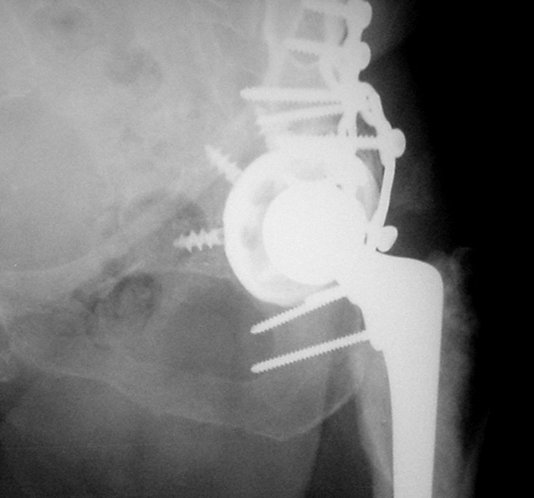

We do not have all information's, like: Judet views, CT, approach used at the time of total hip arthroplasty... what would help, but in general, I would do similar as it is presented with this 75 years old lady:

1. Dislocation of prosthesis

2. Removal of prosthesis head

3. Removal of the cup:we have available some nice, round cutters causing minimal damage of surrounding bone

4. Fix the acetabular fracture (fracture seems to be transverse type!?; it is a real fun to do it with femoral head removed)

5. New metal back cup with multiple holes for screws - improves

osteosynthesis

6. New poly insert and reduction.

7. Femoral fracture - if it is enough space retrograde nail (through the knee), or some plate, fixed angle device.

As you know, in general, if prosthesis is not loose (and from the x-ray cup seems to be well fixed), we do not have to replace it.

1. Problem is that would be very hard to provide good stability - good job fixing the fracture with cup in place, although, of course,it is possible.

2. My preference would be to remove the cup. Having excellent view, approach to the acetabulum and good fixation can be accomplished (this has to be the premice, fracture well fixed before the cup in order to put in it); now, if you use the metal cup with multiple holes, it does work like nice plate and additional fixation to the fracture. If the cup is coated with hydroxy appatite, that will make healing and incorporation even better.